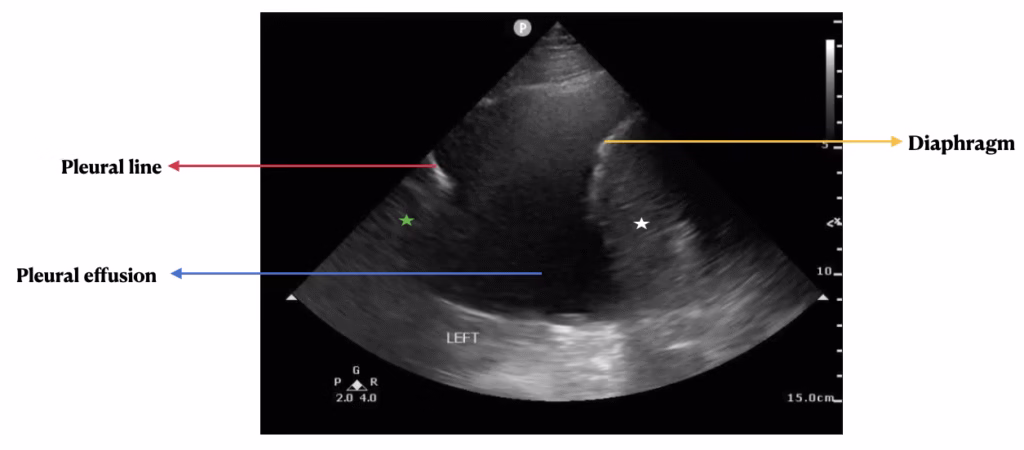

History, physical exam, laboratory, radiological studies, final diagnoses and management decisions were reviewed. We identified three main lung POCUS patterns. These included lung sliding with bilateral A-lines and 0-2 B-lines per lung zone (normal lung POCUS, Figure 1), >2 B-lines bilaterally (predominant B-line pattern, Figure 2) and a predominant A-line pattern with focal, dense B-lines (Figure 3). In addition, patients with unilateral or bilateral pleural effusions (Figure 4) with any of the above patterns were also recorded. Lung POCUS findings were compared with CXRs performed within a 72-hour period, with CT scans, and cardiology-reviewed echocardiograms completed within one month of the lung POCUS examination.

Figure 4. Pleural effusion seen as a hypo-echoic space (blue arrow) flanked by the diaphragm (yellow arrow) with the underlying spleen (white star) and the pleural line (red arrow) with the underlying lung parenchyma (green star).